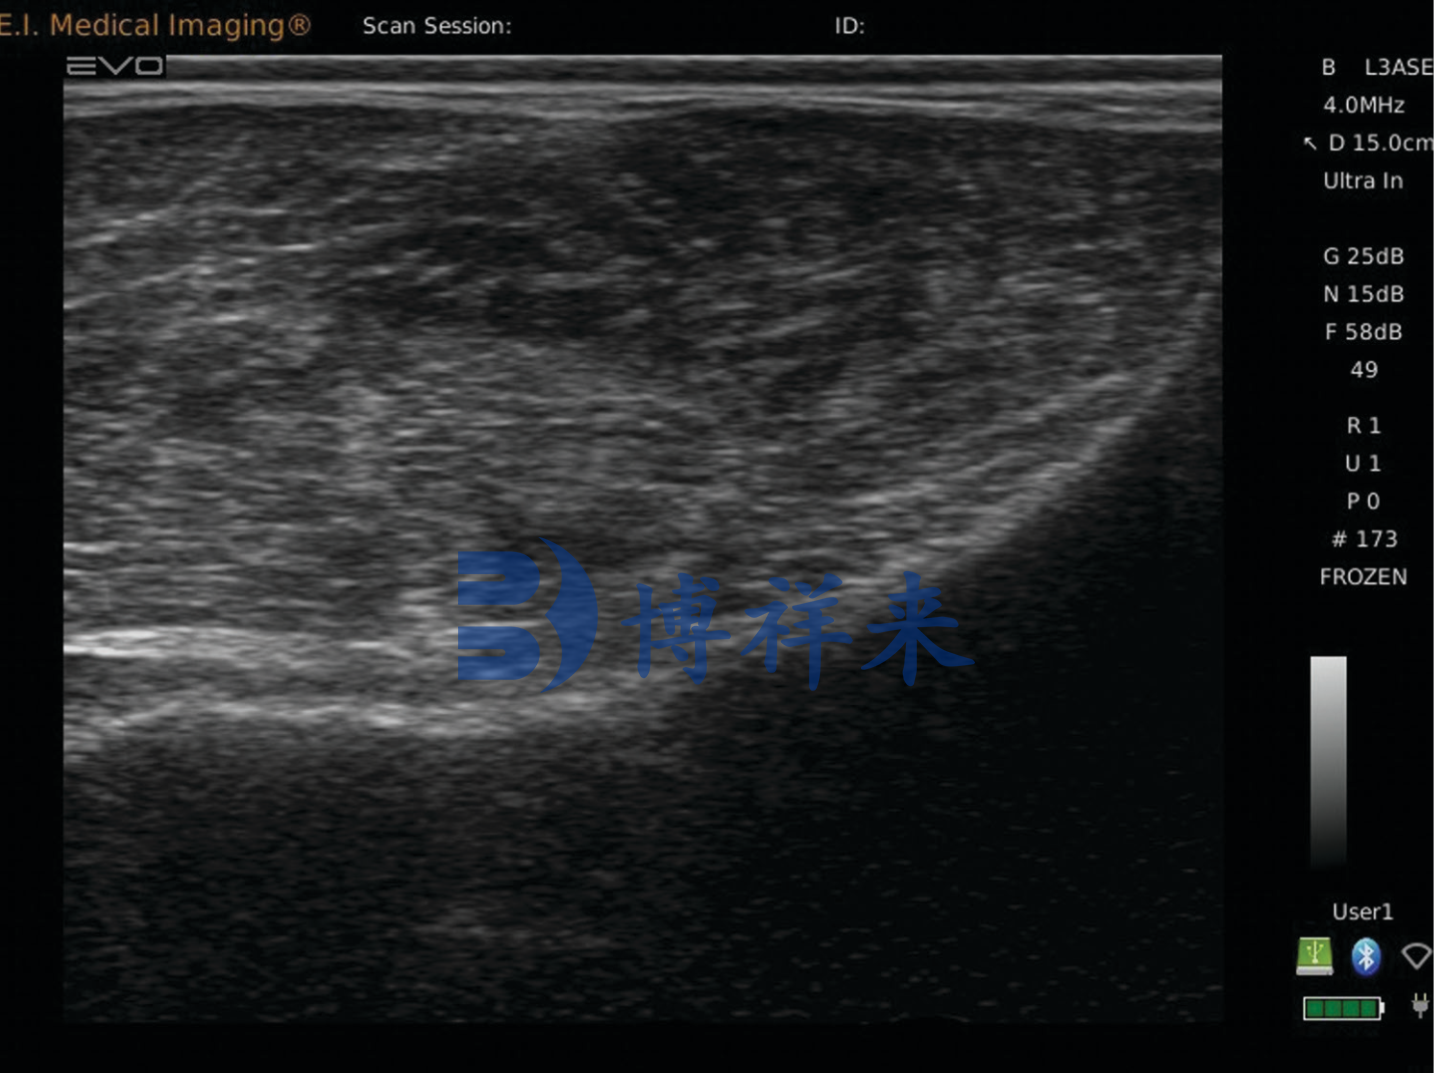

牛臀部脂肪超声图像

脂肪厚度 (FT)

脂肪厚度 (FT) 是对胴体上外部脂肪的评估,并在背最长肌内侧(脊柱)侧到肌肉外侧距离的 % 点处测量。FT 以及最长肌面积与牛肉胴体的零售产品产量高度相关。 较大的脂肪厚度深度导致胴体中零售产品的百分比较低。 产量等级也以数字方式向 5 增加。FT 占牛肉胴体产量等级中发现的大部分变化。 FT 是中等到高度可遗传的。